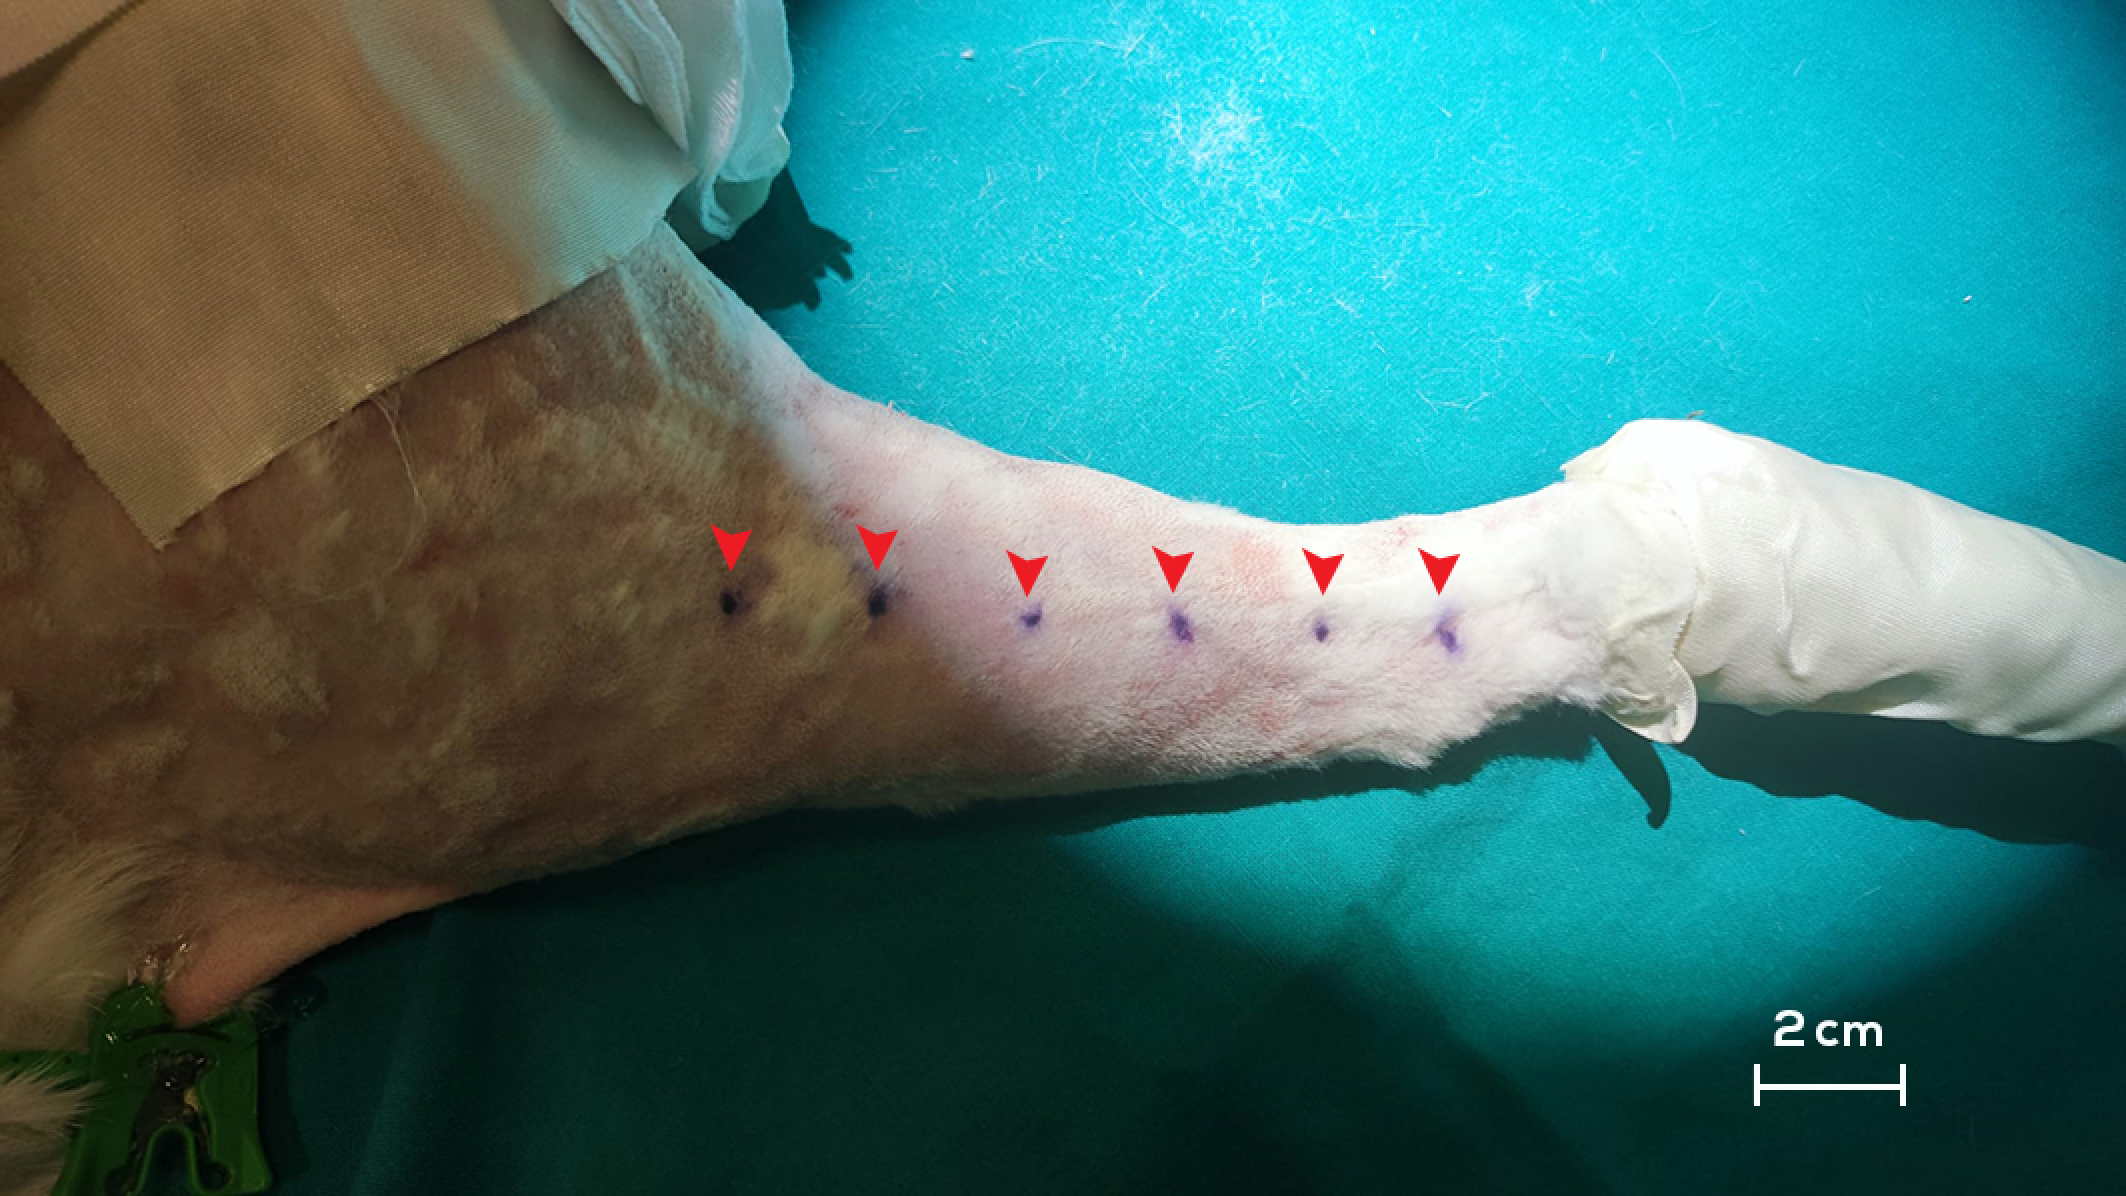

2.2. Intra-Operative Procedures

3.1. Treatment Group (G1)

3.2. Preventive Group (G2)

3.3. Control Group (G3)